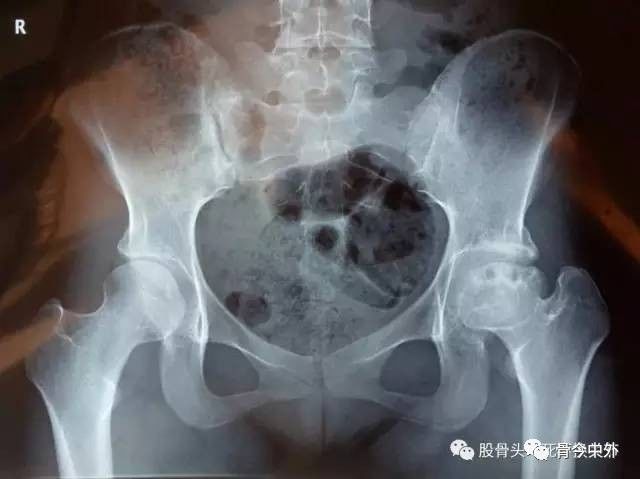

股骨颈骨折是临床常见病,由其继发的股骨头坏死则是众人皆知的疑难病。由于股骨头血运的特殊性,在股骨颈骨折的瞬间,就注定了后期发生股骨头坏死的巨大风险;儿童、青少年患者还会继发股骨近端发育不良、髋关节脱位等病变。

我们无法避免股骨颈骨折继发股骨头坏死,但总有一些措施可以降低股骨头坏死的风险。